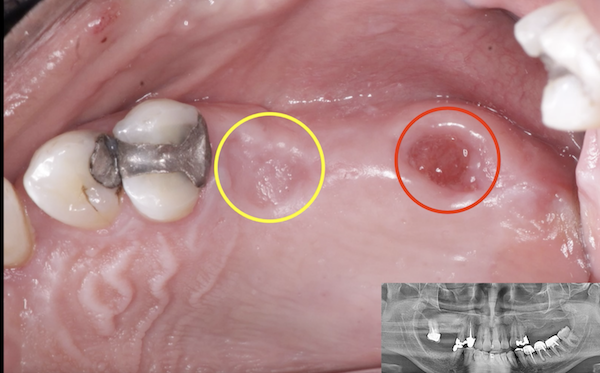

I am feeling really humble. I’ve placed multiple implants and thinking this should be a straightforward case. I was wrong. I know it’s poorly planned and freehand did not go well. Are these restorable? Should I explant and redo? If I do remove these, how easy is it to remove these?